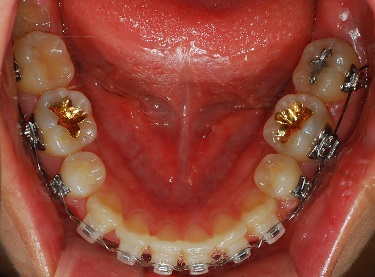

치과쌤이 치아를 쭉보시고 와이어를 얇은것으로 바꿔주셧어요.

드뎌드뎌 치아교정 마무리 작업에 슬슬 들어가는군용!

발치 공간은 다 닫혓어요. ^__________^

(하악사진)

측면에서도 치아 사이에 구멍은 보이지 않아요!